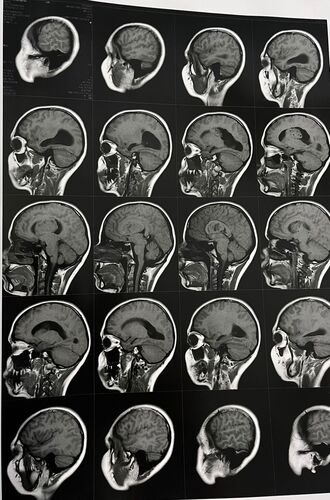

Estamos iniciando esta campanha com um único objetivo: arrecadar recursos para que a Nicoli possa realizar uma cirurgia delicada no cérebro. Recentemente, ela foi diagnosticada com um tumor cerebral, que requer avaliação especializada e procedimento cirúrgico com urgência.